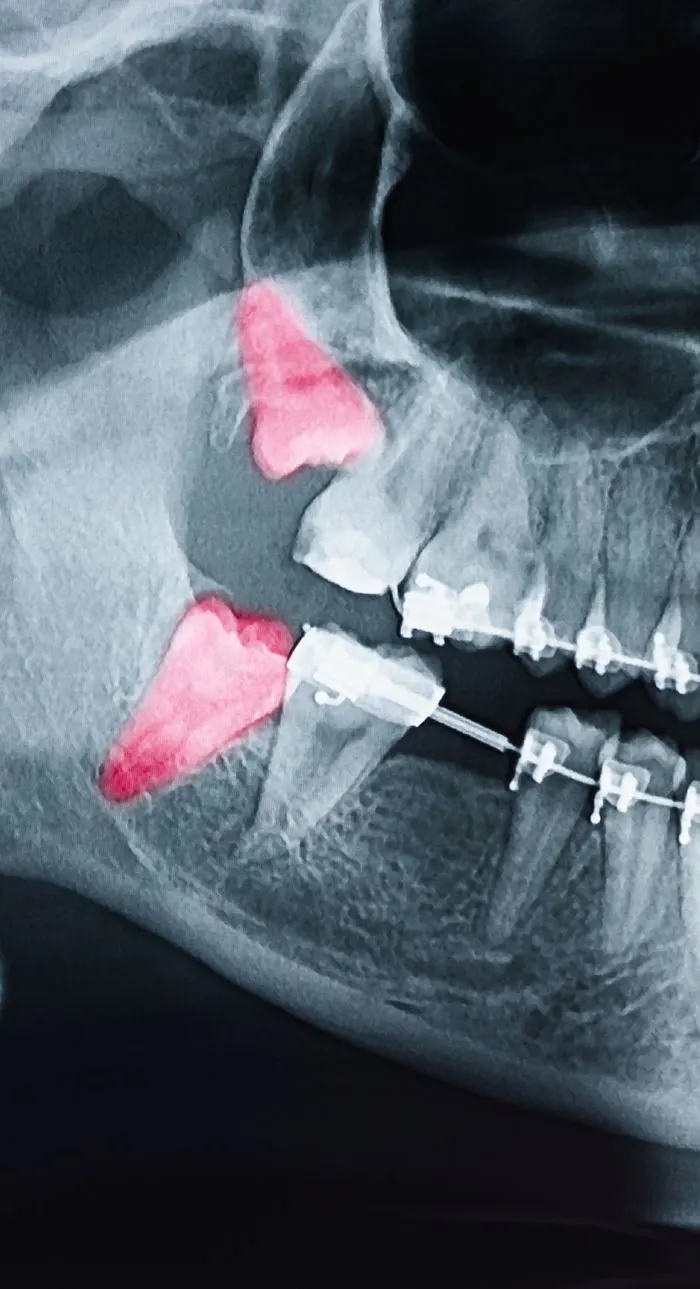

With digital x-rays, we get high-resolution images of your teeth that allow us to make more accurate diagnoses. When you’re in pain or experiencing an emergency, we can see why the tooth is reacting and if an extraction is needed.

During your consultation, we’ll take digital x-rays to assess the condition of your tooth and the surrounding bone. We’ll explain whether extraction is truly necessary and walk you through any alternatives. If you’re moving forward, we’ll review the number of teeth to be removed, aftercare expectations, and any follow-up recommendations for tooth replacement. We’ll answer every question you have so you feel fully informed and know what to expect.